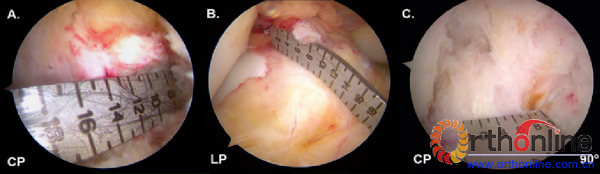

首先对ACL股骨和胫骨止点的大小进行测量,(图6)根据尺寸选择进行单束还是双束重建,并帮助选择直径合适的移植物。止点前后径需要如果小于14mm,则不宜选择双束重建,而适合单束解剖重建。

图6:右膝关节屈曲90度,关节镜下使用测量尺对止点进行测量。

图7:右膝关节屈曲90度,中间入路观察的关节镜示图。该图比较了三种钻取AM股骨隧道的方式:A、经AM胫骨隧道钻取;B、经PL胫骨隧道钻取;3、经前内辅助切口钻取。通过比较,只有经前内辅助切口才能使导针到达AM股骨解剖位置。